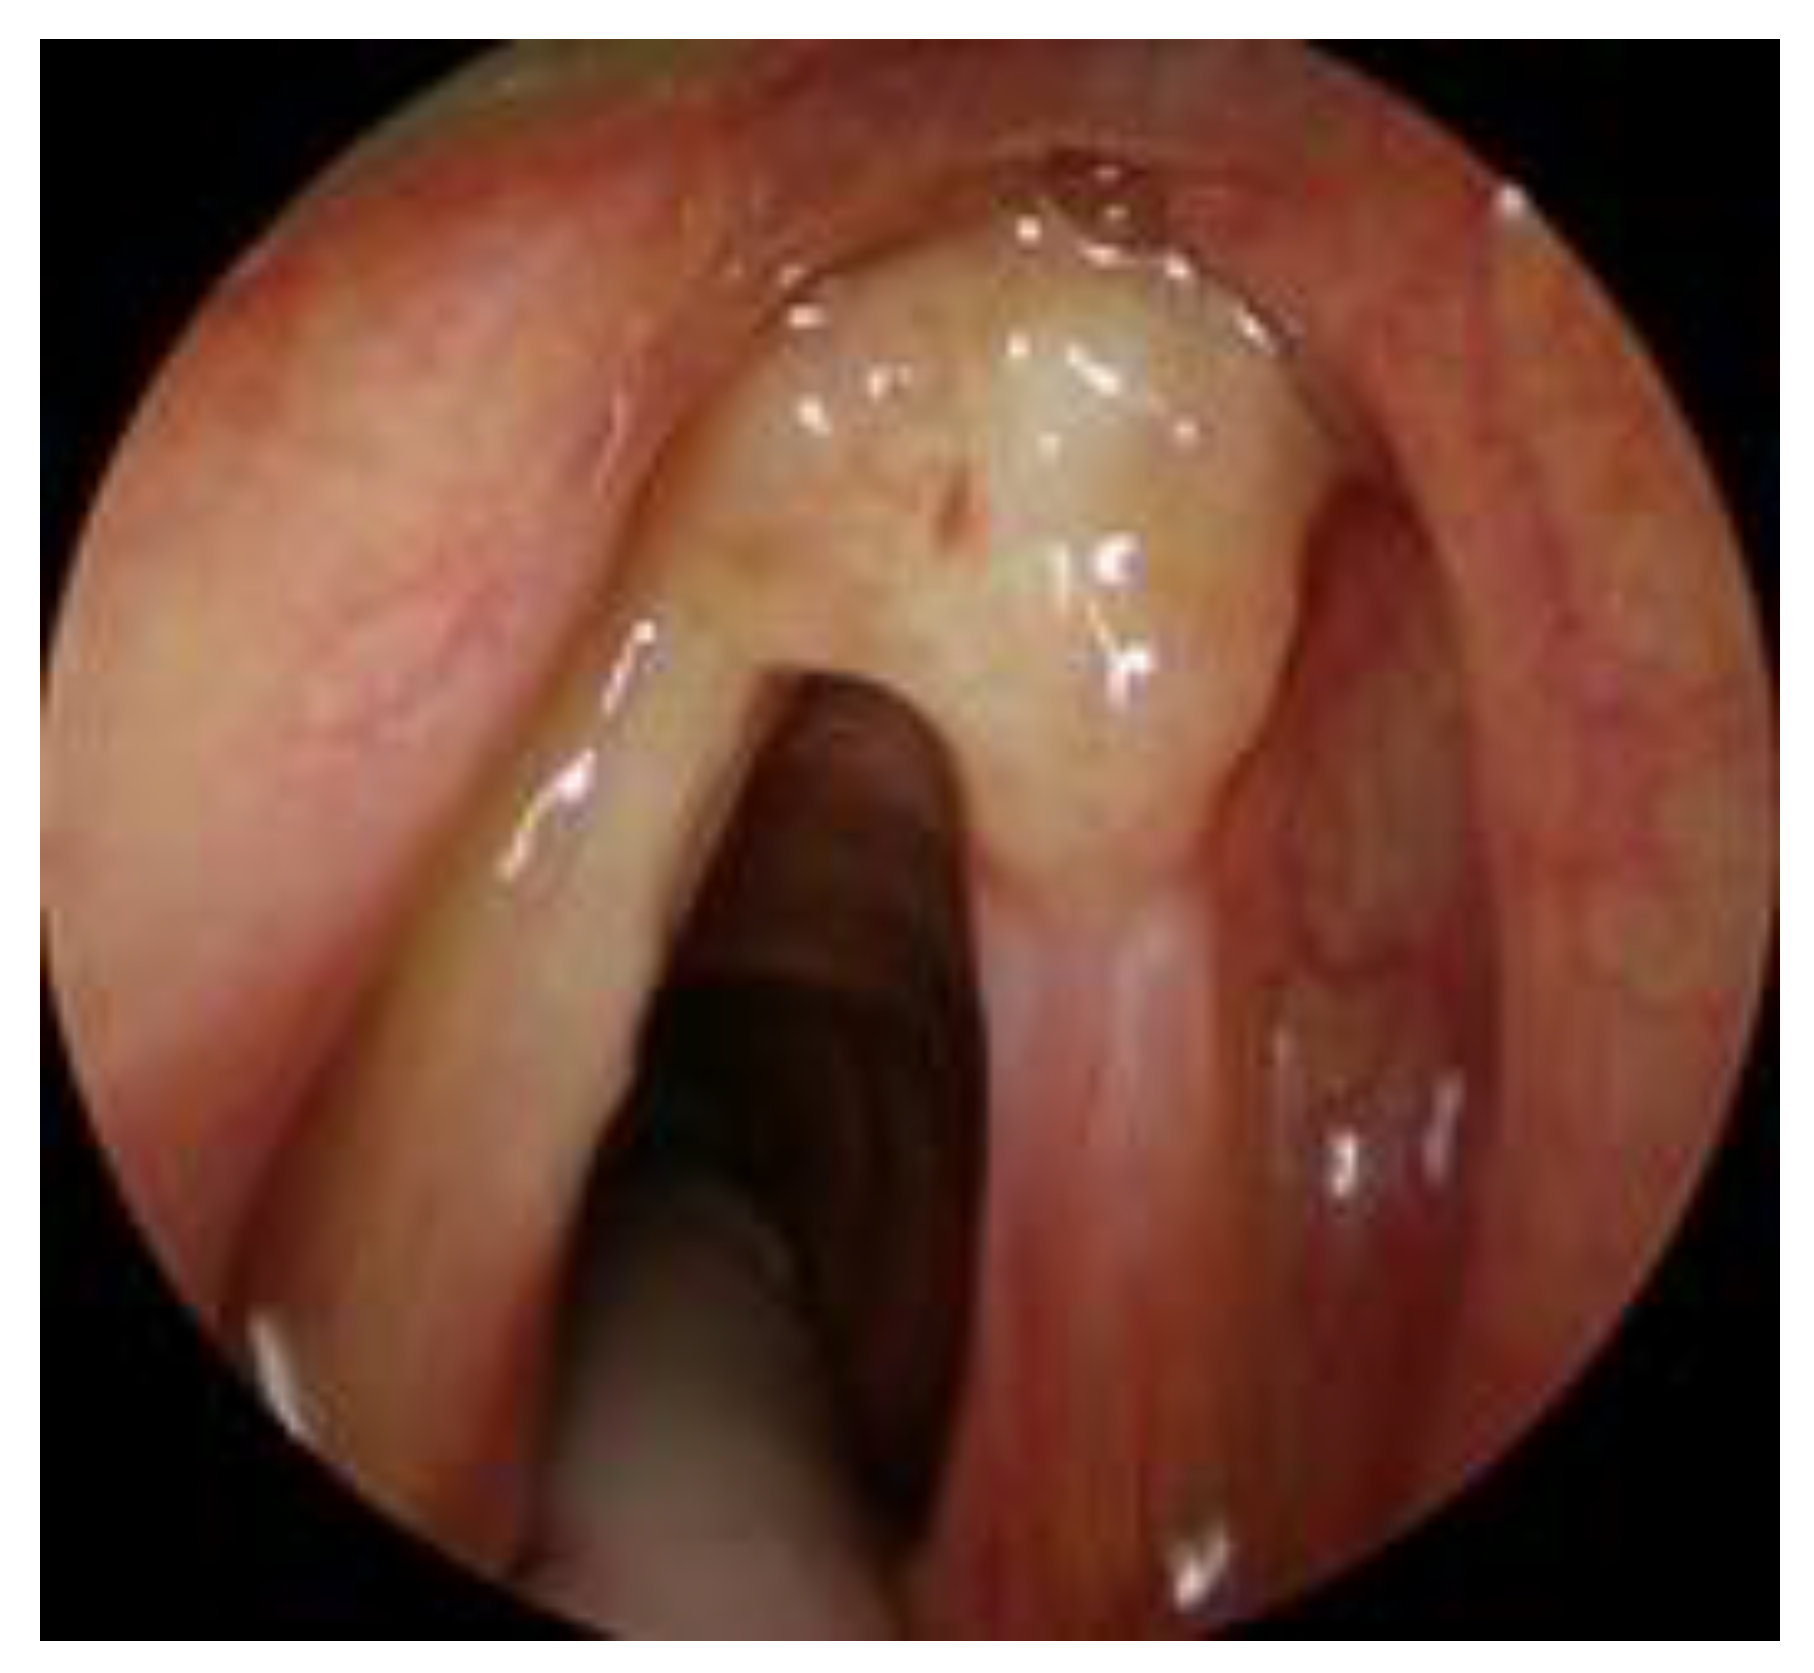

- T1b with AC, tumor involving one or both vocal cords, with AC involvement, with normal vocal cord mobility (Figure 3).